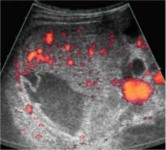

визуализации дефекта паренхимы печени на момент осмотра (рис.1 а.).

размеров дефект па-ренхимы (рис.1 б, в). Здесь же отмечалось отсутствие органного сосудистого

рисунка при сохранении его в неизмененных участках паренхимы печени.

| а - сканирование в правом подреберье через 4 часа после травмы. В проекции правой

доли печени определяется значительных размеров зона гетерогенного повышения эхогенности.

Небольшое количество жидкостного компонента подкапсульно. |

б - через 9 часов после травмы при сканировании в В-режиме из косо-поперечного

доступа в эпигастрии определяется значительных размеров дефект паренхимы правой

доли печени (анэхогенный участок неправильно-овальной формы). |

в - 9 часов после травмы, тот же доступ, сканирование в режиме

энергетического допплера. В проекции дефекта паренхимы печени определяется бессосудистая

зона. В неповрежденных участках паренхимы сосудистый рисунок сохранен. |